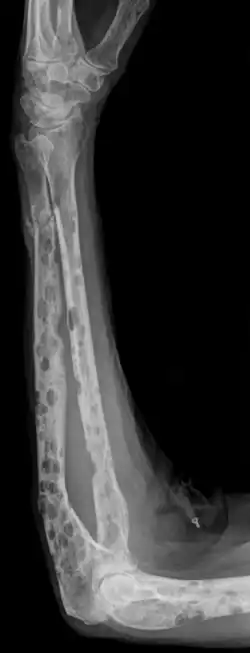

- Starker Knochenabbau/-schäden durch Osteolyse (die Schäden wirken im Gegensatz zu Knochenmetastasen wie ausgestanzt – typisch: Schrotschussschädel)

- Durch die Osteolyse bedingte Knochenschmerzen und Knochenbrüche

- Knochenläsionen mit mindestens einer osteolytischen Läsion, nachweisbar durch Röntgen, CT oder PET-CT.